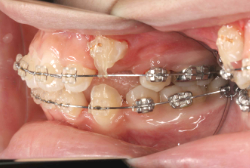

「乳歯が生え替わらない」という主訴で来院したケースです。 診断の結果、「左上永久犬歯が第一小臼歯後方上部に埋伏しているため、左上乳犬歯が晩期残存している症例」と判明しました。

このような症状の場合は、手術で埋伏している永久歯に金具を取り付け、矯正装置で牽引する必要があります。同時に凸凹の解消と前突した前歯を内側に入れるために上下左右の小臼歯を抜歯させて頂くことといたしました。

この方の場合は、マルチブラケット装置にて治療を開始し、治療期間2年3ヶ月で終了しました。犬歯の牽引距離が非常に大きかったため当院の平均治療期間よりも大幅に期間がかかりましたが、埋伏犬歯を完全に正しい位置まで誘導することができました。同時に 前歯の前突と配列の凸凹も解消しました。

マルチブラケット装置は、装置装着時より数日から2週間程度強い不快感疼痛が有りますが、本症例場合は埋伏歯を開窓手術し、遠く離れた位置に矯正器具が付いていますので強い違和感が生じ、歯ブラシも届きにくく口腔衛生状態を保つのにはかなりの努力が必要です。条件の悪い場所に接着されているため、装置が外れやすく日常生活上もかなり配慮が必要となります。

また、埋伏歯は移動距離が大きくなることが多く、歯根吸収のリスクが高まりますので、移動と休止にゆとりのある治療間隔が必要です。